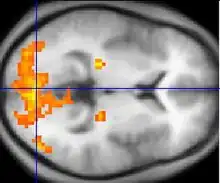

Neuroimaging

Neuroimaging has contributed to the identification of the neural components involved in drug reinstatement as well as drug-taking determinants such as the pharmokinetics, neurochemistry, and dose of the drug. The neuroimaging techniques used in non-human primates include positron emission tomography (PET), which uses radiolabeled ligand tracers to measure neurochemistry in vivo and single-photon emission computed tomography (SPECT).[3] Functional magnetic resonance imaging (fMRI) is widely used in human subjects because it has much higher resolution and eliminates exposure to radiation.[14]